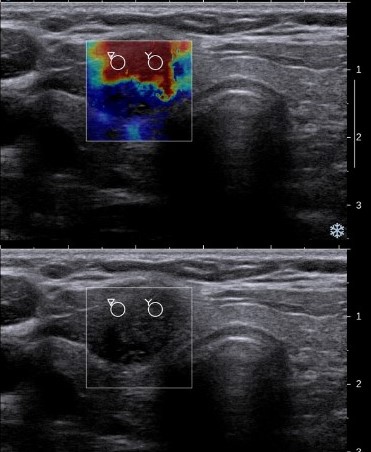

Elastography

الاستوگرافی تکنیکی است که سختی یا خاصیت ارتجاعی بافتها را اندازهگیری و به صورت تصویر رنگی نمایش میدهد. این روش برای تشخیص تودههای سرطانی، آسیبهای کبدی و بافتهای فیبروتیک کاربرد دارد.

از نظر فیزیکی، با اعمال موج مکانیکی (ارتعاشی) به بافت، میزان جابجایی و تغییر شکل آن اندازهگیری میشود. بافتهای سختتر تغییر شکل کمتری دارند و در تصویر با رنگهای متفاوت نمایش داده میشوند.